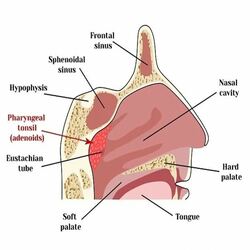

Uvulopalatopharyngoplasty (UPPP) is a surgical procedure to eliminate extra tissues. This procedure increases the oropharyngeal airspace by resecting tissue in the throat, including one or more of the following:

- The uvula the soft flap that hangs down at the back of the throat.

- Parts of the soft palate and tissue at the side of the throat.

- Tonsils and adenoids in the even they are present.

Tonsillectomy and adenoidectomy: These procedures are used to remove the tonsils and/or adenoids may be needed to prevent snoring.